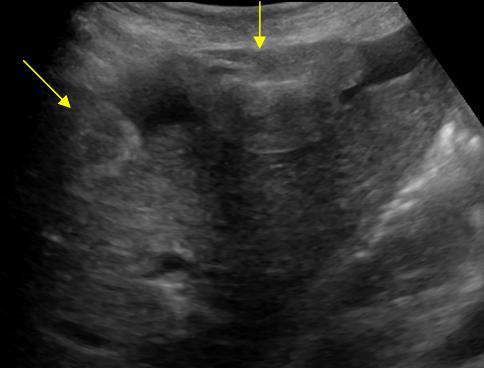

Di căn phúc mạc - Ảnh 3

Di căn phúc mạc

» Thông tin: Nữ giới – 55 tuổi.

» Lâm sàng: Đau bụng / K buồng trứng.